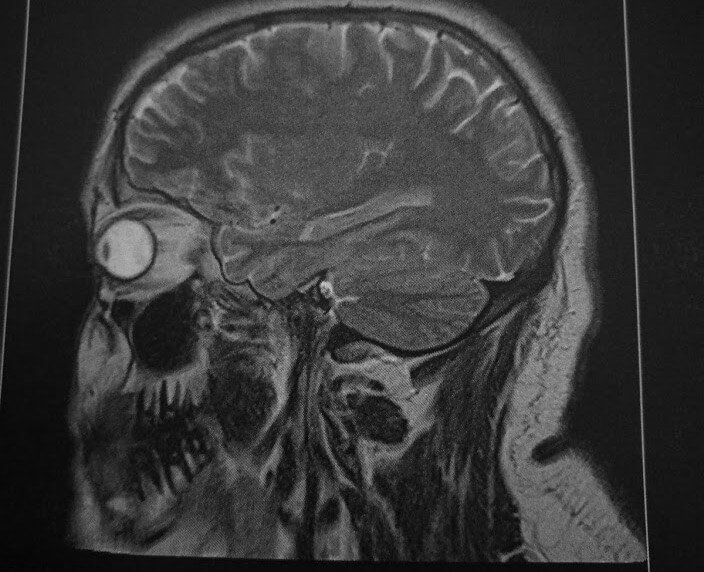

Seither nehme ich in nicht normalem Ausmaß Kortisontabletten, Kortisonnasensprays oder Kortisonnasentropfen, testweise auch mal Tabletten gegen Morbus Menière (weil ich es – selten aber doch – auch mit sehr starkem Schwindel zu tun hatte), normalen Schwindel-/Reisekrankheittabletten, zwischendurch auch mal wieder Antibiotika und klassischen Nasen- und Meersalznasensprays zu mir. Ich weiß seit November: Ich passe auch in ein MRT. Und könnte man bei Hörtests irgendetwas auswendig lernen, ich hätte das bereits längst geschafft. Das Ergebnis: Es geht immer wieder bergauf und auch bergab. Es ist und bleibt spannend.

Als ich im August erstmals das Wort „Tieftonhörsturz“ gehört hab, habe ich es nicht gleich begriffen. Ganz ehrlich … es brauchte noch bis Ende September, bis ich das erste Mal gecheckt hab, dass das offenbar nicht so leicht weggeht. Nach mehrmaligen Besuchen bei meiner HNO-Ärztin und einem MRT-Check, um ein Akustikneurinom (so ein gutartiger Tumor im Kleinhirn oder so) auszuschließen, schockte mich schließlich einer der Ärzte in der HNO-Ambulanz. Er war der erste und wohl auch der ehrlichste, der mir die Chancen erklärt hat: In 33 % der Fällen wird es wieder besser, in 33 % der Fällen bleibt es gleich und in 33 % der Fällen wird es schlechter und kann bis zur Vertäubung führen. Und ganz ehrlich: Davor habe ich richtig Schiss. Das ist auch der Grund, warum ich alles nur erdenklich Mögliche der Schulmedizin ausnutzen möchte. Ich habe Kortison nun bereits intravenös und mehrfach mit einer Spritze durchs Trommelfell durch ins Mittelohr bekommen (hört sich schlimm an, aber es ist relativ unspektakulär). Aktuell steht auch ein kurzer stationärer Eingriff im Raum, bei dem man das Trommelfell wegklappt und direkt an der Außenhülle des Innenohrs arbeitet. Ein weiteres, genaueres MRT ist in den kommenden Wochen geplant. Alles für das Gehör!

Das Beitragsbild ist übrigens ein Schnappschuss von meinen MRT-Aufnahmen.